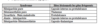

Quelles sont les divisions de l’arc aortique?

Quelles sont les 3 artères formant la circulation cérébrale antérieure?

Quelles sont les 5 branches de l’artère carotide interne?

Quelles sont les 2 grandes artères formant la circulation cérébrale postérieure?

Quelles sont les 5 branches de l’artère vertébrale?

Quelles sont les 5 branches de l’artère basilaire?

Qu’est-ce que le polygone de Willis?

Quelles sont les 5 artères constituant le polygone de Willis?